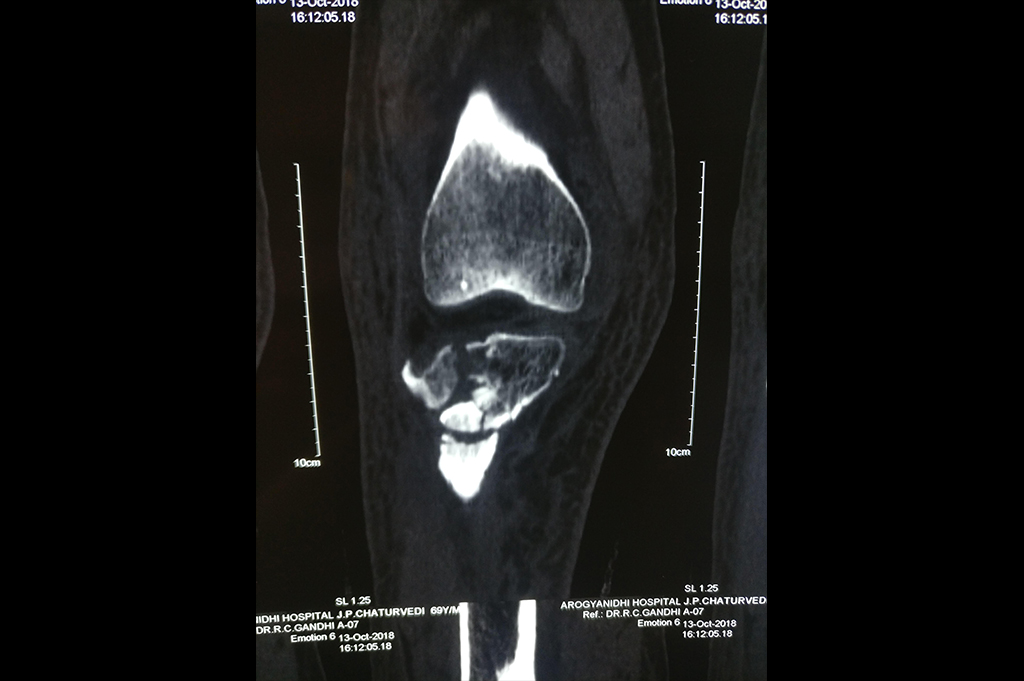

Calcaneum